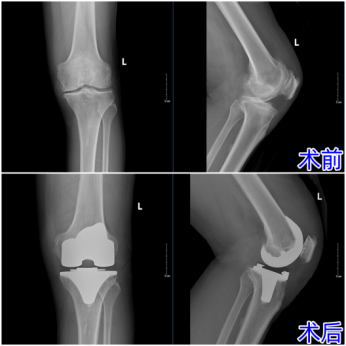

吴大哥深受重度膝关节炎困扰,行走疼痛不稳,日常活动受限,生活质量大打折扣。他慕名来到济南南郊医院骨科就诊,经全面影像检查,确诊左膝重度退行性病变,合并半月板损伤、滑膜炎及软骨磨损,属典型重度膝关节骨性关节病。骨科杨学良主任指出,患者膝关节多结构受损,保守治疗已难缓解症状,人工膝关节置换术是当前最合适的治疗方案。

经骨科医护团队专业护理与康复指导,吴大哥恢复顺利。术后复查显示假体对合良好、下肢力线正常。目前其关节活动度逐步改善,疼痛基本消失,正接受后续康复训练。